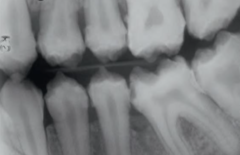

dentinogenesis imperfecta on radiograph

Front

Back